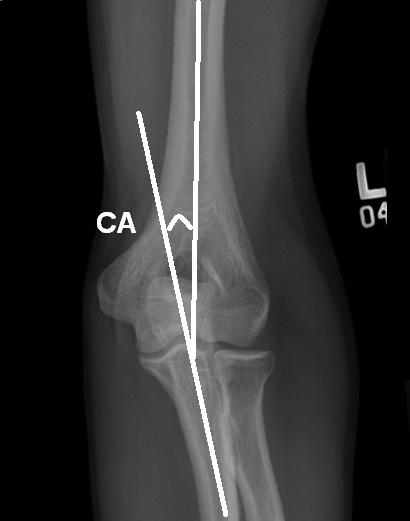

ELBOW

DEFINITION:

angle formed between the long axis of humerus and long axis of the ulna

ABNORMAL:

if < 154 degrees then gunstock deformity

if > 178 degrees then supracondylar fracture ( RID4650 )

how to draw the carrying angle of the elbow